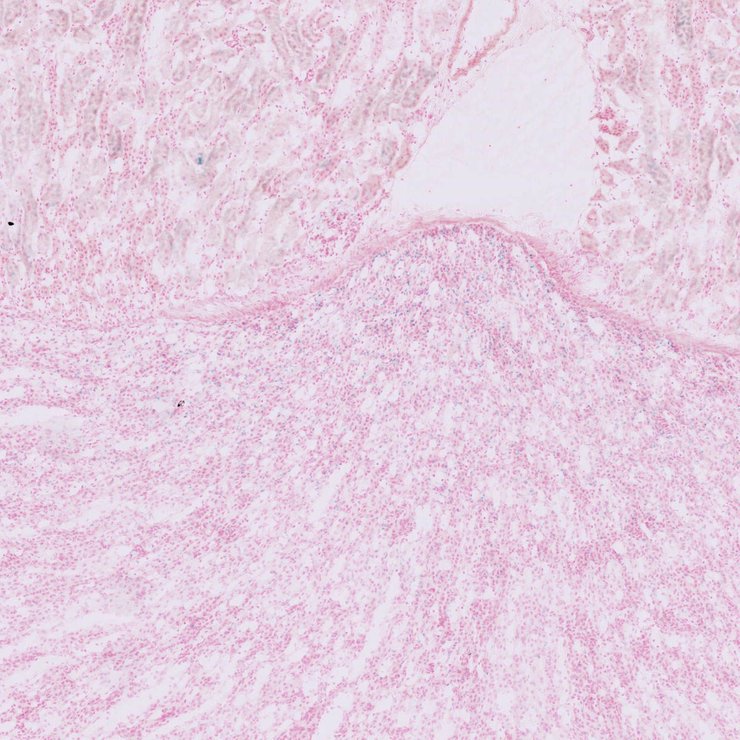

TS28: uterus Present JAX_1801751